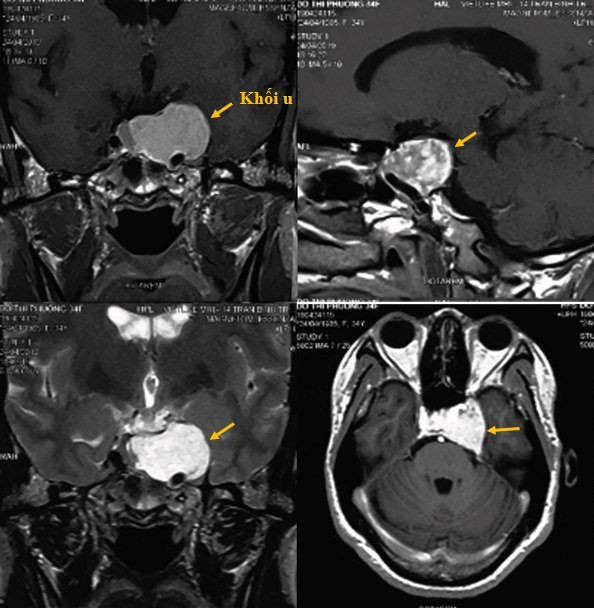

Bệnh nhân N.T.H (34 tuổi, Hà Nội) biểu hiện chủ yếu đau đầu kéo dài, nhìn đôi, tê bì, thái dương... Kết quả chụp MRI cho thấy u trong xoang tĩnh mạch hang chèn ép tuyến yên.

Hình ảnh u máu trong xoang tĩnh mạch hang của bệnh nhân trước phẫu thuật